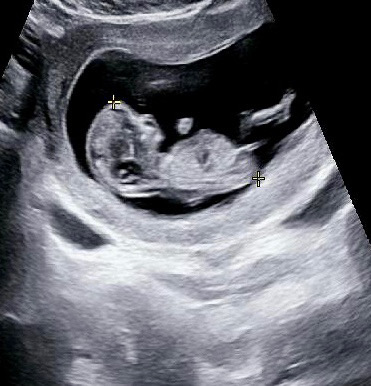

각도법 봐주세요!

11주 6일 입니당! 니프티도 했는데 결과 기다리기 힘드네욧ㅋㅋㅋㅋ